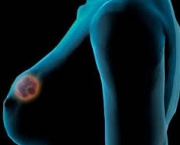

- Cirurgia em Oncologia.

Especialistas apontam faltar definições práticas sobre as cirurgias plásticas no Sistema Único de Saúde. De acordo com a versão no Ministério da Saúde a cobertura apenas acontece para corrigir lesões, defeitos e deformações. Ou seja, possuem características congênitas ou adquiridas no sentido de melhorar as condições de saúde do paciente, com classificação de reconstrutora ou reparadora. Nesse sentido se convém dizer que não se cobre apenas por causa da finalidade estética.

Outro exemplo considerado clássico e utilizado por Douglas Jorge como alerta está nos problemas de mulheres com excesso de seios. Não é novidade inclusive ao senso comum que elas possuem problemas por conta da postura, dores nas costas, feridas nos ombros por causa do peso exercido no sutiã, entre outros problemas.

Porém, grande parte das pacientes não está na situação de extrema urgência. Jorge tem dúvidas quanto ao nível de grau autorizado pelo SUS. Sem contar que representa o erro clássico de reparar apenas quando acontece o pior ao invés de tomar medidas preventivas.

O especialista diz que o problema está no fato do grupo de cirurgias classificarem como procedimentos relacionados com estética ou embelezamento, coisas que na verdade estão ligadas de modo exclusivo para a saúde do ser-humano.